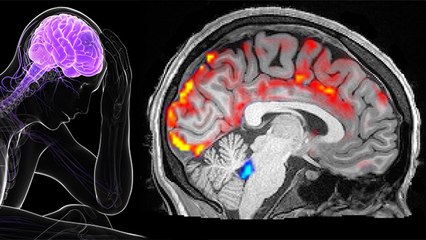

टीवी का रिएलिटी शो 'बिग बॉस 17'दर्शकों का खूब मनोरंजन कर रहा है. शो में आए कंटेस्टेंट्स भी दर्शकों की पसंद बन रहे हैं. शो में एक कंटेस्टेंट ऐसा है जिसने बचपन में ही जिंदगी और मौत की जंग लड़ी है. जी हाँ, इनको ब्रेन ट्यूमर था पर इन्होने उस बीमारी का कैसे इलाज किया और उसके बाद ये कैसे ठीक हो सके, चलिए आज की वीडियो में जानते है. br br TV's reality show 'Bigg Boss 17' is entertaining the audience a lot. The contestants who came to the show are also becoming the choice of the audience. There is a contestant in the show who has fought the battle of life and death since his childhood. Yes, he had brain tumor but how he treated that disease and how he recovered after that, let us know in today's video. br br #Lifeafterbraintumor, #Braintumoriscurable, #Kyabraintumortheekhosaktahaibr ~HT.178~PR.266~ED.